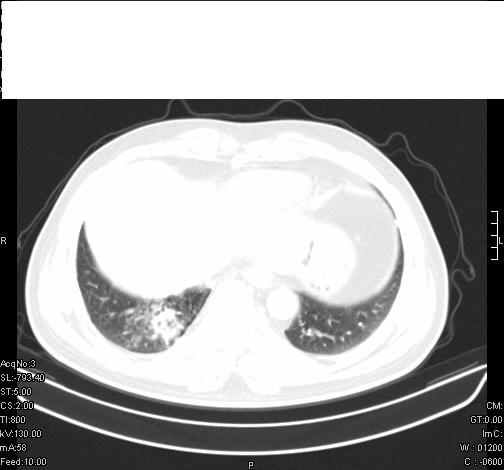

前几天,发了患者的平扫片,患者抗炎一周后增强扫描。右中叶病灶吸收明显,但下叶病灶未见明显吸收。右肺门可见结节影,看来凶多吉少

右肺下叶支气管管腔狭窄,管壁增厚,右下肺见斑片状高密度影,考虑右侧肺门中心肺癌伴阻塞性肺炎

右肺下叶散在的斑片状致密影,下叶支气管变窄。考虑:右肺慢性炎症。

右肺下叶支气管壁不规则增厚,右肺下叶有斑片状影分布。考虑右肺中央型肺癌伴右肺下叶阻塞性改变。建议支纤镜检查。平扫比增强较好显示了病变情况。

既然抗炎治疗有效,可继续治疗;右肺下叶支气管管腔狭窄,管壁增厚,右下肺见斑片状高密度影,右侧主支气管后见结节影(淋巴结?),肺癌不能排出。